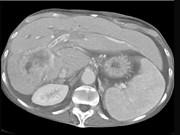

问题 男,50岁,右上腹痛,进行性黄疸,无腹部包块,AFP阴性,影像检查如图,最可能的诊断是()

选项 A.肝细胞肝癌 B.胆管癌 C.肝血管瘤 D.肝腺瘤 E.肝转移瘤

答案 B